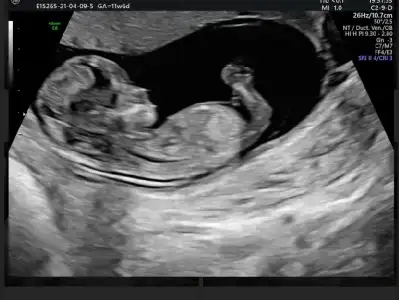

Kız sanki emin olamadım başka USG varsa paylaşınMerhabaIkra meyra 'cım. Benim de 12+4 ultrason görüntüm. Bize de tahmin de bulunabilirsen çok mutlu olurum